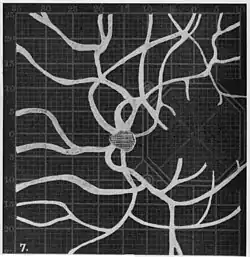

Angioscotomas were first discovered and mapped out by John Norris Evans (1891-02-28--1953-04-08)[2] in 1926, who coined the term angioscotometry to describe the painstaking charting of the scotoma of the retinal blood vessels by manual perimetry. He seated each subject in a seat in a dark setting, and tested whether they could see a tiny bright test object placed at various locations.[3] Using a 1.5 mm white disk, Evans reported intricate branch‑like scotomas that mirrored the arteries and veins emerging from the optic disc, with a full map requiring up to 2 hours to complete. He plotted this for subjects under various conditions, such as while holding breath, with glaucoma, etc. A year later, he confirmed that only short stump‑like scotomas had been noticed previously, some further data plotted with a smaller 1 mm stimuli, and under varying conditions on the subject.[4] He published a monograph on this in 1938 in which he described its use in assisting diagnosis of various conditions, such as retinal edema, glaucoma, optic neuritis, etc.[5]

Using eccentric fixation, the more nasal parts of the angioscotoma can be plotted. -

1. Pressure on globe shows only stumps of large vessels. 2. Holding the breath causes similar effect; also 3. Holding the head low. 4. Pressure on opposite eye widens arteries and still more veins, 5. Pressure on the carotid produces no definite effect. 6. Looking thru red glass brings out finer vessels. -